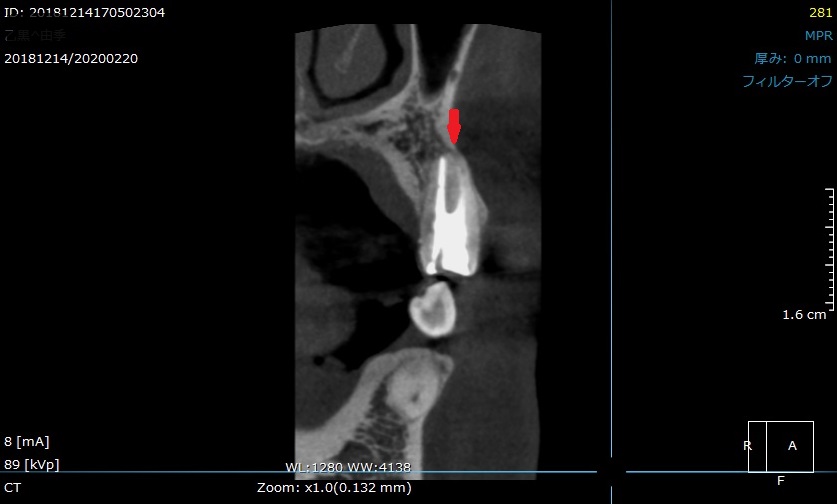

最初に来院された時のCT画像です。

矢印の先に黒い影があります。

すでに神経を取って、根管治療がされています。